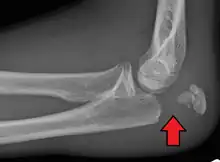

Powerful pull of the triceps muscle can also cause avulsion fractures.

- Type II - Avulsion (displaced)